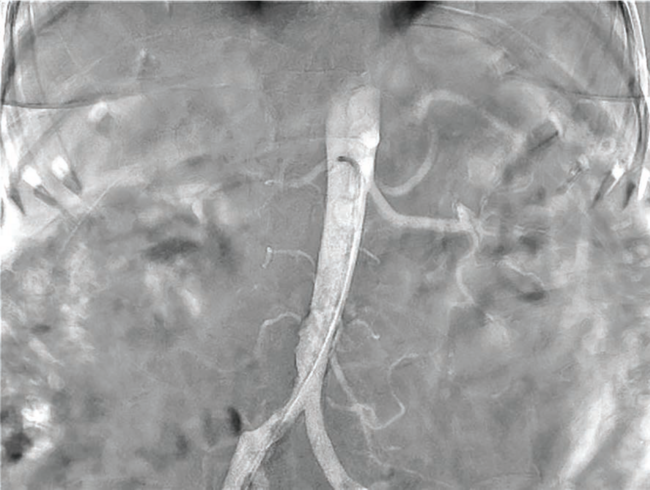

Renal denervation can be performed safely on a same-day basis. Our approach is as follows. We bring patients in the morning and our procedure starts with conscious sedation administered by our cath lab nurses. We sometimes use the sedentary effect of Benadryl to complement safe administration of conscious sedation. There are currently two approved RDN platforms: the Spyral catheter from Medtronic requires a 6 French (F) femoral artery sheath and the Paradise catheter from Recor Medical requires a 7F sheath. Once femoral artery access is obtained, we look at the abdominal aorta and renal arteries. We first make sure that no significant disease exists in the proximal portion of the artery. We don’t want to treat renal arteries with disease greater than 50% in severity. We also want to exclude renal arteries with signs of other conditions like fibromuscular dysplasia. Second, we look for accessory arteries and find those arteries meeting the size criteria, which is between 3 and 8 millimeters (mm). Size is usually not an issue for the main renal arteries, but accessory arteries of at least 3 mm can allow for treatment, which is critical as these arteries often have substantial nerve innervation, similar to the main renal artery branches. Once we have visualized the anatomy and excluded severe atherosclerotic disease, we will bring up a renal guide for selective angiography. We like to have a few shapes available and prefer the shorter lengths (~55 cm), but this procedure can be done through a traditional 90 cm guide. The internal mammary artery (IMA) guide and renal double curve (RDC) guide are the typical shapes we start with. We take a selective angiogram of each main and accessory artery, as well as document a full baseline nephrogram. We typically give intra-arterial nitroglycerin up front when we do the angiogram to try and size all branches at maximal vasodilation, and then again at the end of the procedure to ensure there is no vascular trauma.

Good imaging is extremely helpful to guide us throughout the case. It is important to have the capability for digital subtraction angiography (DSA). When we do the non-selective aortogram to lay out the branches and the aorta, we do that on DSA. We want to see everything. We want to see the anatomy, if there is any disease in the renal arteries, if accessory arteries are present, what landmarks we can use for catheter engagement and that the full renal is perfused. Thus, it is critically important to have a good imaging system. We then need our imaging system to help us unfold vessel branches that are projecting 2-dimensionally but are really in 3 dimensions. These branches can come off at different angles and tortuosities, and appear overlapped. Appropriate projections are needed to understand which arteries are candidates for treatment and how we will wire these different branches. It is also very helpful, once the anatomy has been established, to be able to use those images for roadmaps or reference overlays in a peak opacity format, which allows us to avoid additional acquisitions and contrast injections. Lastly, it all comes down to patient safety. We must be able to try to limit our scope of view and get a good high-quality image, but also not use too much radiation where the patient or the provider is being overly exposed. We rely on a high-quality system to provide the required imaging needs and preserve safety. These capabilities are particularly important for renal denervation, which has been made better by our ability to use new technology and a newer system to launch this newer procedure.